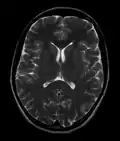

![]() Cross-sectional T1-weighted MRI of a healthy human brain acquired with an ultra high-field MR of 7 Tesla field strength | |

- T2-weighted (T2W) images: CSF is light, but fat (and thus white matter) is darker than with T1. T2-weighted images are useful for visualizing pathology.[26]

Normal axial T2-weighted MR image of the brain